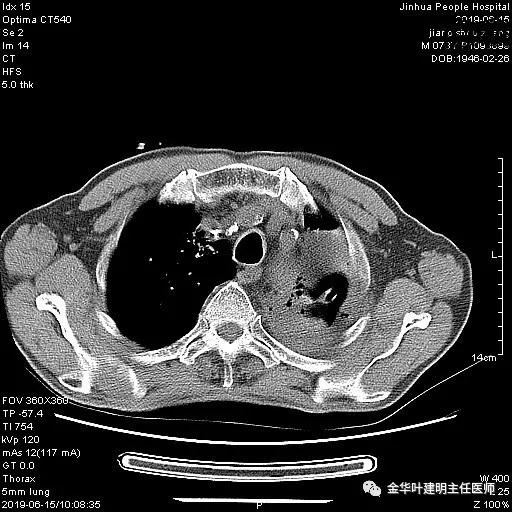

考虑左侧大量胸腔积液,遂进一步胸部CT检查:

以上是肺窗表现,下面为纵隔窗影像: